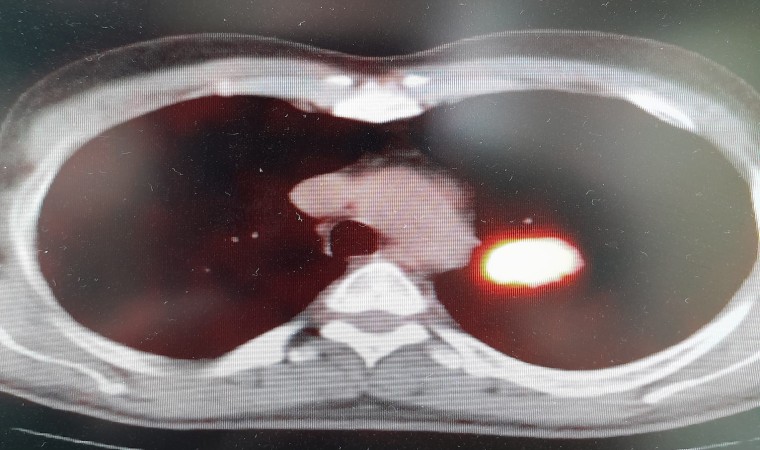

Prof. Dr. Şevket Özkaya, yaptığı değerlendirmeyle önemli uyarılarda bulunarak, “Eğer sigara kullanıyor veya kanserojen maddelere maruz kalıyorsanız, bu kansere yakalanma yaşınızı düşüren bir faktör. Örneğin; 150 veya 170 yaşında akciğer kanseri olacak bir kişi, sigara içtiği için bu yaş 100’e düşüyor. Eğer ailede kanser öyküsü varsa bu yaş daha da düşüyor. Ve 45 yaşından sonra her an kanser gelişmesi ile karşı karşıya kalınıyor” diye konuştu. Bu durumda kişiyi kanserden kurtaracak en etkili yöntemin erken tanı ve tedavi olanakları olduğuna dikkat çeken Özkaya, pandeminin kanser konusunda topluma önemli bir katkısı olduğunu anlattı. Covid-19 nedeniyle başvuran hasta sayısında ve radyolojik görüntülemelerde yaşanan artışın birçok vakanın erken evrede saptanmasını sağladığını belirtti.

Kanser söz konusu olduğunda hastalara “hastalıktan korkma, geç kalmaktan kork” dediklerini belirten Özkaya, “Çünkü kanser, erken evrede yakalanırsa tamamen kurtulabileceğiniz bir hastalıktır. Sağlık Bakanlığımızın kanser taramaları için kurduğu Kanser Erken Teşhis Tarama ve Eğitim Merkezleri ‘KETEM’ birimleri yıllardır bu konuda çok başarılı işlere imza atıyorlar. Topluma en faydalı sağlık hizmetlerinden biri olarak halkımıza kadın ve erkek kanserleri için erken tanı ve tedavi hizmetlerini ücretsiz olarak vermeye devam ediyorlar” diyerek erken tanının önemini vurguladı.